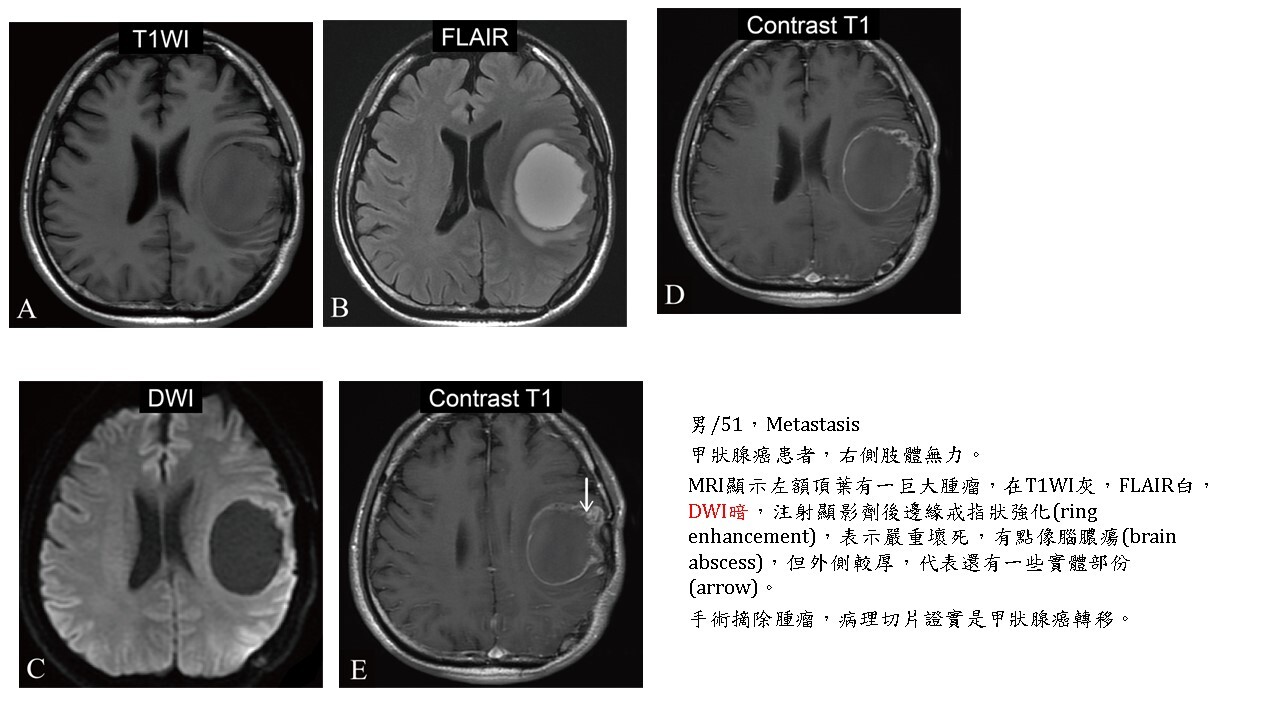

腫瘤囊化(cystic change)或壞死(necrosis)部分,呈現類似CSF訊號,即在DWI暗,ADC白。

大多數的腫瘤(brain tumors)的實體部分(solid part),不管良性及惡性,DWI都會稍白,但對於血管豐富的hemangioblastoma, hemangiopericytoma則DWI暗。